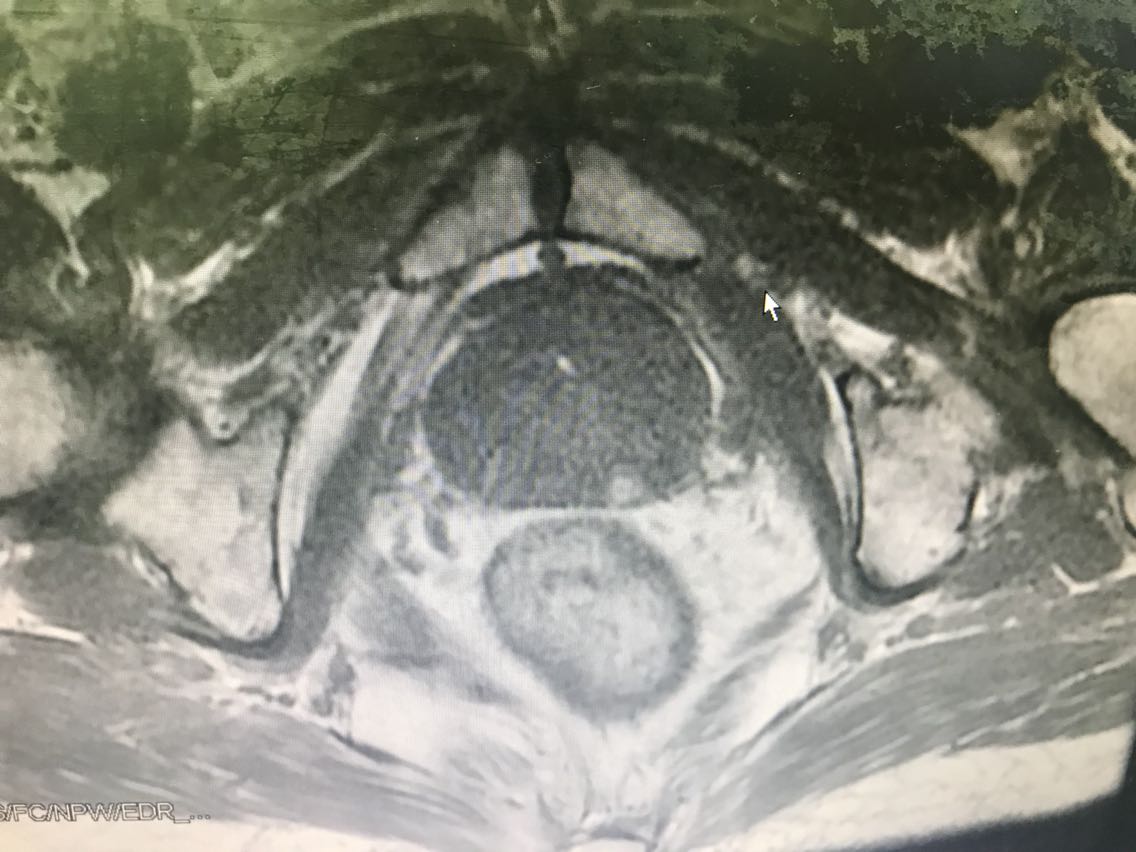

患者男性,77岁。 主诉:血尿7+月 现病史:入院前7+月,患者出现血尿,于外院体检查示PSA升高(10.62),服药血尿控制(具体药物不详),无尿频、尿急、下腹疼痛等不适,为求进一步诊治于我院门诊就诊,查前列腺MRI:前列腺尖部右侧中央带结节及9-10点结节,多系前列腺癌。门诊行前列腺穿刺活检示:编号1、2、3、4、5、6查见前列腺腺癌,Gleason评分4+3=7分。门诊以“前列腺癌”收入我科。患病来精神、睡眠、食欲可,大小便无异常,体重无明显变化。 既往史无特殊。

查体:腹部平软,无压痛及反跳痛,双肾及输尿管走行区无压痛,肾区无叩痛。直肠指检:前列腺Ⅱ°大,双侧质硬,右侧叶扪及约1cm硬结。 辅助检查: 前列腺MRI(2018-6-14,本院):前列腺尖部右侧中央带结节及9-10点结节,多系前列腺癌,累及右侧外周带 前列腺穿刺活检示(2018-6-28,本院):编号1、2、3、4、5、6查见前列腺腺癌,Gleason评分4+3=7分。